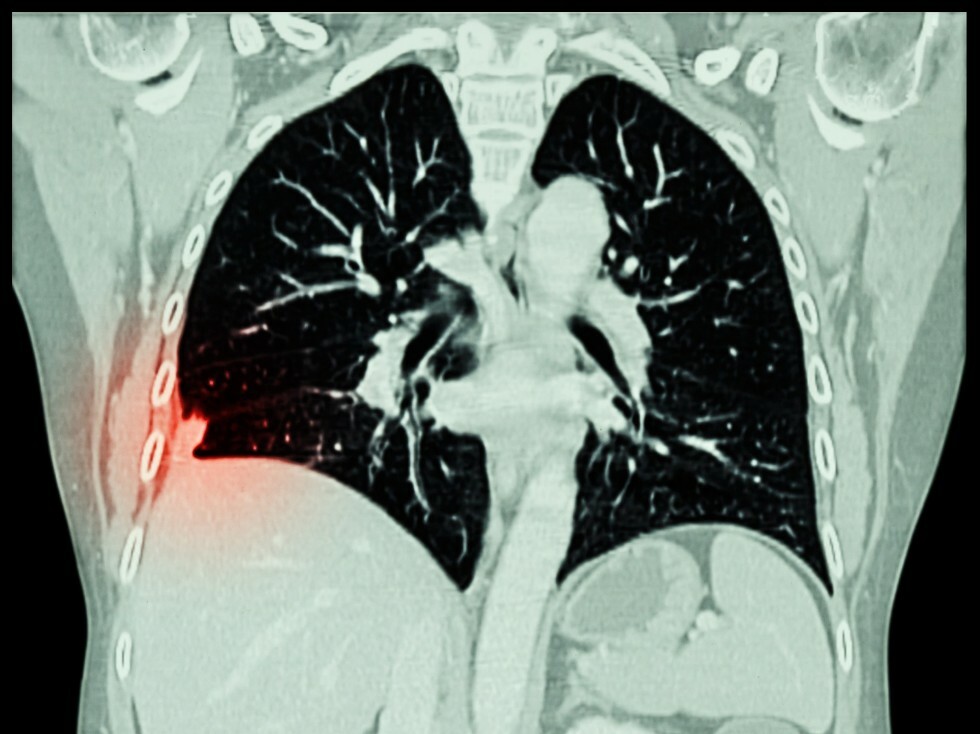

CT - Chest

A CT scan of the chest is a type of scan that uses special equipment to obtain cross-sectional images of the organs and tissues of the chest. The images produced are far more detailed than those from a traditional chest X-ray. This scan can simultaneously show many different types of tissue including the lungs, heart, bones, soft tissues, muscle, and blood vessels.

Why might my doctor recommend a CT of my chest?

A CT of the chest may be recommended for a variety of reasons. First, it can be used to detect tumors that develop in the lungs or that have spread there from other parts of the body. It also can be used to screen for lung cancer that may not be found on a chest X-ray. Other lung disorders, such as old or new pneumonia, tuberculosis, emphysema, and lung disease can be detected by this scan as well.

CT - Lung Cancer Screening

Why is CT scanning used to detect lung cancer?

A CT of the chest is used to take high-resolution pictures of the lungs, allowing for the detection of abnormal spots called nodules. These nodules usually are too small to be seen on a chest X-ray. Studies show that low-dose CT screening greatly increases the likelihood of detecting lung cancer at an earlier and more curable stage than chest X-rays. According to researchers:

• Using CT, nodules were detected three times as often as on chest X-rays.

• Malignant tumors were detected four times as often as on chest X-rays.

• Stage I (the earliest stage of invasive lung cancer) malignant tumors were detected six times as often as on chest X-rays.

• Malignant tumors detected using CT were substantially smaller, meaning they were detected earlier, than those detected on chest X-rays.